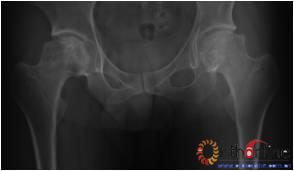

图3-2 女,30岁,SARS患者骨坏死,(1)术前MRI示双侧骨坏死;右Ⅱc期C3型,左Ⅱb期B型,打压植骨术(加BMP2),(2)5年后CT显示病灶修复好,关节功能优